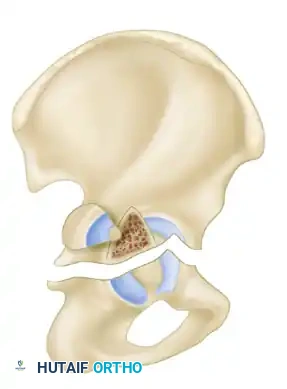

- Both-Column Fractures: The most complex pattern. All articular segments are detached from the intact posterior ilium (which remains attached to the sacrum).

Clinical Pearl: The Spur Sign

In a both-column fracture, the intact portion of the ilium (attached to the sacroiliac joint) projects laterally relative to the medially displaced, fractured acetabular columns. On an obturator oblique radiograph, this intact bone appears as a sharp spike, known as the "Spur Sign." Its presence is pathognomonic for a both-column fracture.

Secondary Congruence in Both-Column Fractures

A unique phenomenon observed exclusively in both-column fractures is "secondary congruence." Because all articular fragments are detached from the axial skeleton, they can occasionally settle concentrically around the medially displaced femoral head.

If the articular cartilage space is preserved and the femoral head remains concentrically enveloped by the fragments (despite medialization of the entire joint complex), nonoperative treatment via skeletal traction can yield surprisingly excellent long-term functional results.